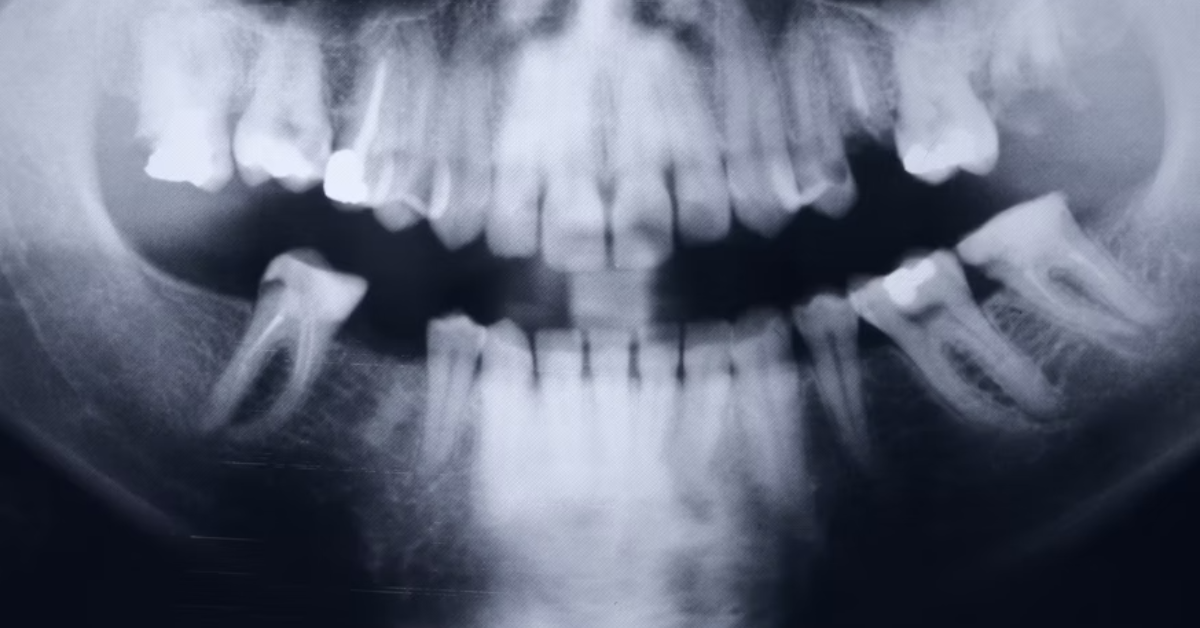

The early signs usually appear as firm bumps or ridges beneath the gum, particularly on both sides of the lower jaw. Tori can be unilateral (one-sided) or bilateral (both sides). They tend to grow very slowly and may remain the same size for many years. Dentists can easily identify tori through visual inspection and X-ray imaging, ensuring that they are not mistaken for cysts, tumors, or other pathologies.

Patients are advised to maintain proper oral hygiene, as plaque accumulation around the tori can irritate the surrounding tissue. Regular dental visits ensure that any changes are detected early. It is also essential to avoid self-diagnosis; while tori are harmless, other conditions like osteomas or cystic lesions may present similarly. “A simple panoramic X-ray can confirm the diagnosis,” notes Dr. Lydia Kim, oral radiologist. “Understanding whether a growth is physiological or pathological can prevent unnecessary anxiety.”